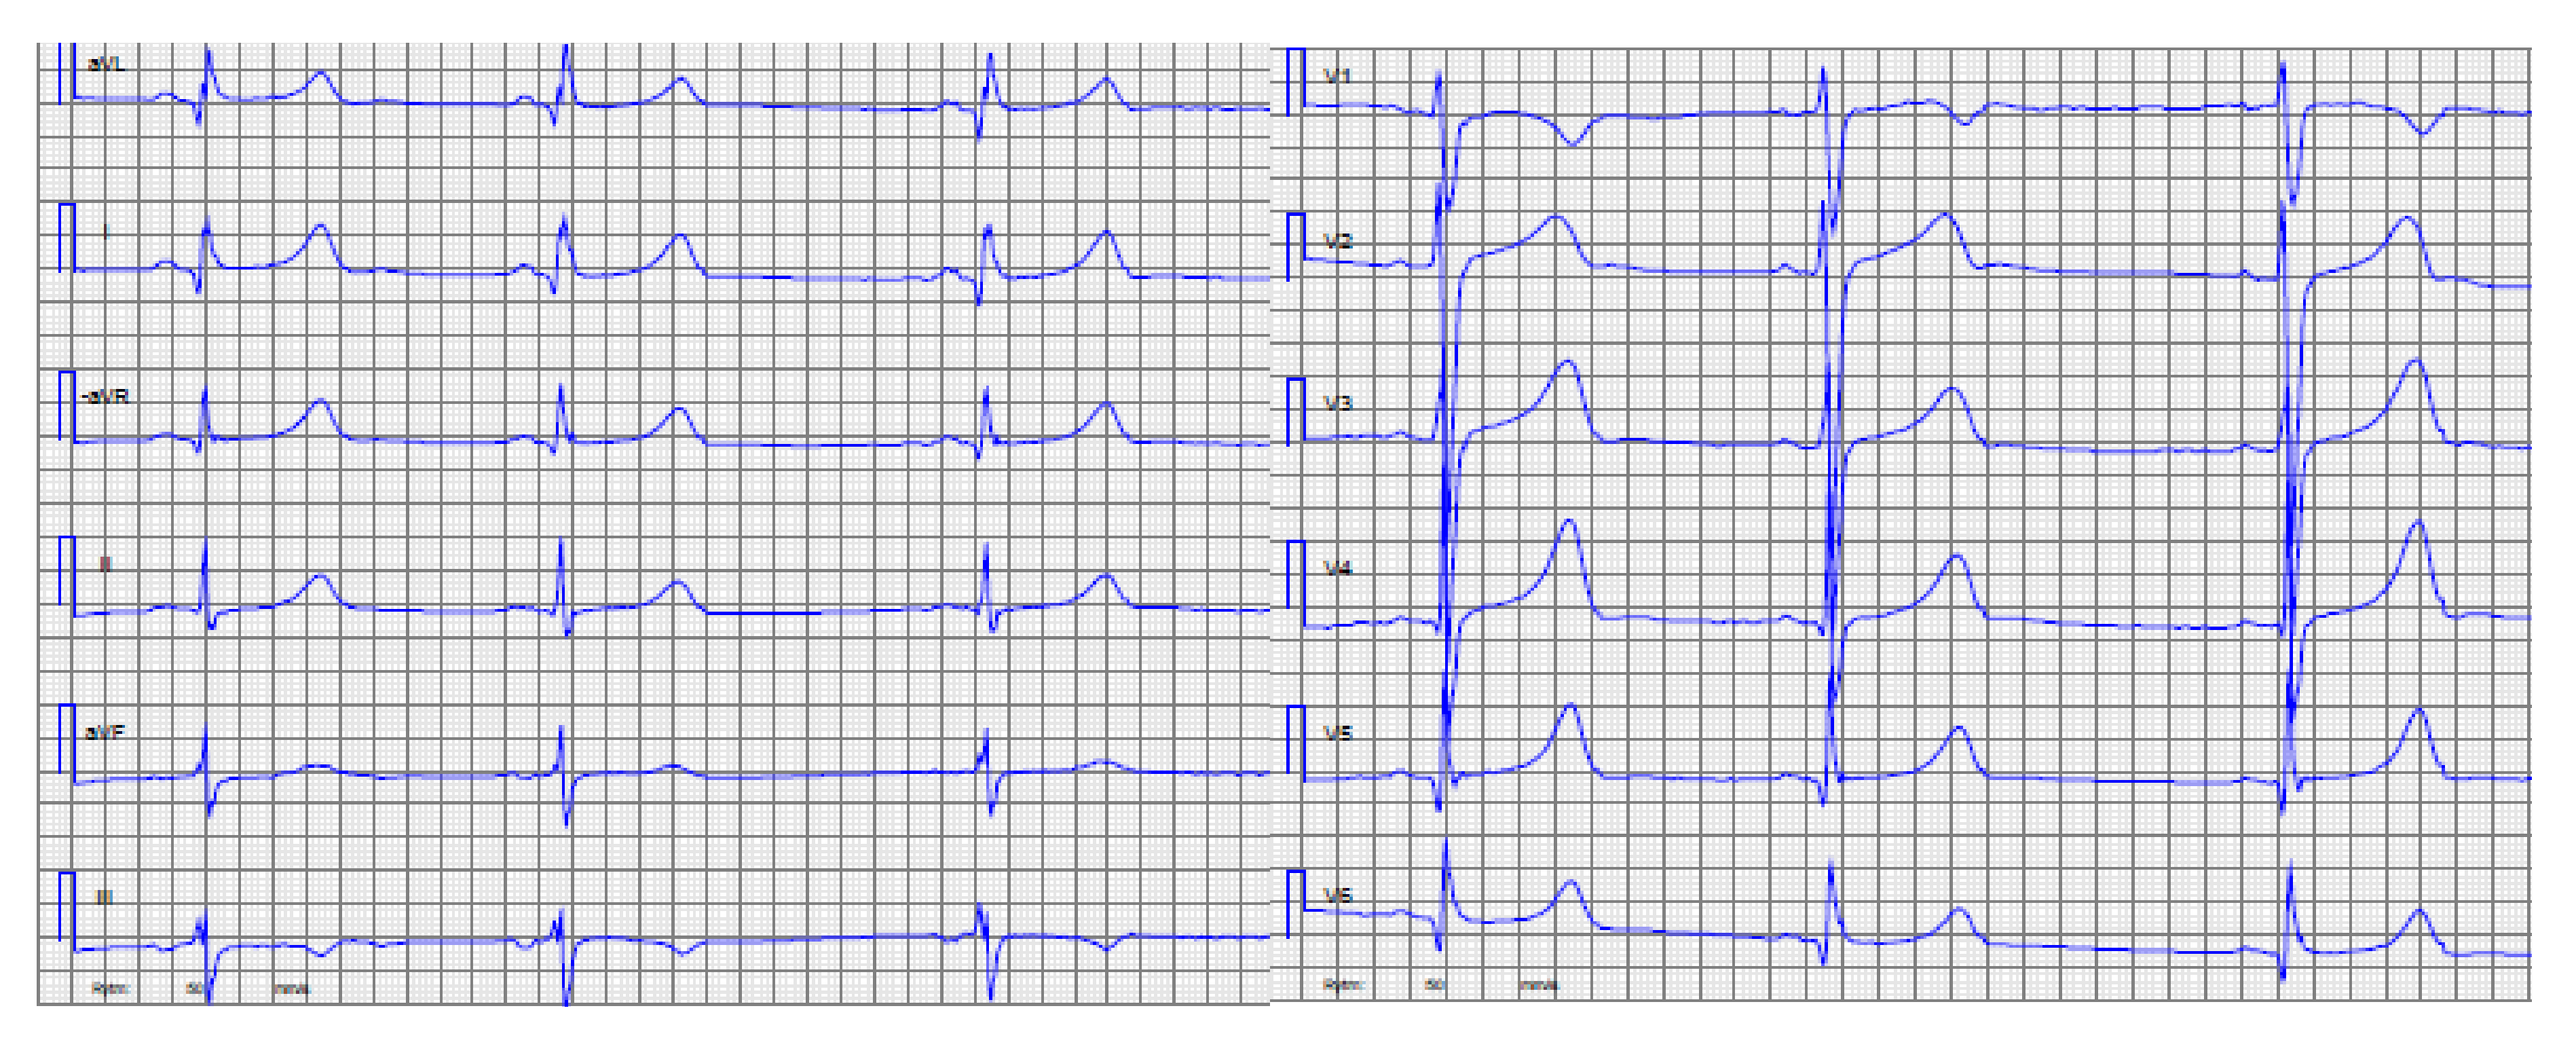

| 2. | I:1 | 22 | M | 1 | Apical LVH | 2 | 8 | Mother SCD due to HCM | No result | No result |